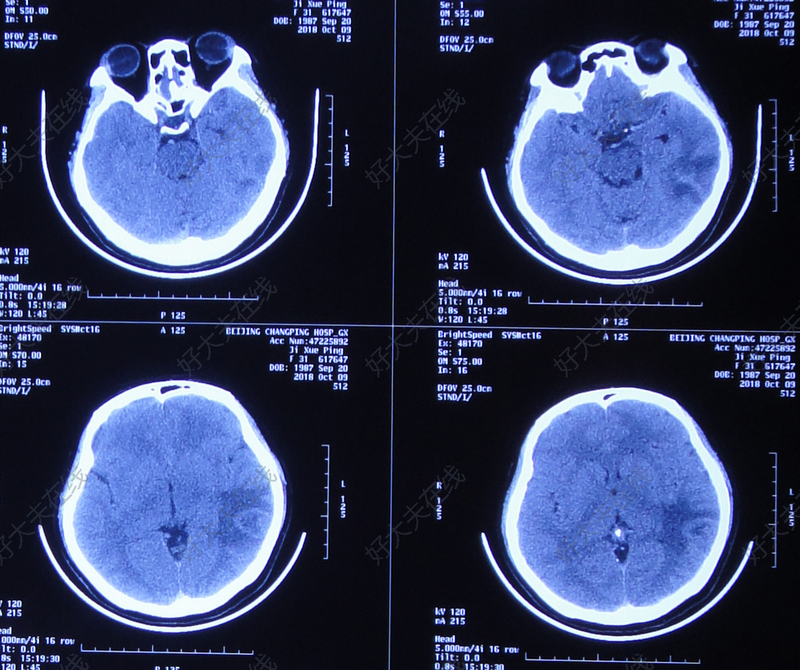

顱內(nèi)感染合并腦積水比較常見(jiàn),部分顱內(nèi)感染后期會(huì)形成腦膿腫,膿腫形成后不能簡(jiǎn)單的依據(jù)腦脊液化驗(yàn)結(jié)果判斷何時(shí)停止抗感染治療以及何時(shí)分流。因?yàn)槟摫诘母綦x作用讓細(xì)菌局限在膿腔內(nèi),腦脊液并不能反映真實(shí)的顱內(nèi)感染情況。小膿腫壁厚的情況下可以選擇保守治療,體積較大壁薄者不建議存有僥幸心理,尤其是緊鄰腦室壁的,一旦破裂后果極其嚴(yán)重。該腦膿腫患者在前期增強(qiáng)頭MRI陰性,并不是感染控制住了,而是在早期釓劑增強(qiáng)需要延長(zhǎng)時(shí)間,所以沒(méi)有發(fā)現(xiàn)。因該膿腫體積大、壁薄、緊鄰腦室,因此必須處理。我們選擇微創(chuàng)內(nèi)鏡下清理膿腔,清除附壁的膿苔和硬化的膿液,抗生素沖洗后通過(guò)監(jiān)測(cè)下的負(fù)壓讓膿腔閉合,注意負(fù)壓不合適可能導(dǎo)致出血和腦室壁開(kāi)放。術(shù)后第二天患者體溫恢復(fù)正常未再發(fā)燒。經(jīng)過(guò)兩周的治療,膿腔消失。

6. 腦膿腫做如何選擇做CT或MRI檢查?1. 頭顱CT掃描診斷腦膿腫的敏感性不如MRI,但在緊急情況下CT通常更容易實(shí)施。當(dāng)尋找腦膿腫時(shí),CT檢查必須給予對(duì)比劑?!裨缙谀X炎呈不規(guī)則的低密度區(qū)域,在注入對(duì)比劑后顯影不強(qiáng)化。●隨著腦炎進(jìn)展,病灶增大,在注射對(duì)比劑后,病變呈現(xiàn)厚的、彌散性的環(huán)形強(qiáng)化。環(huán)形強(qiáng)化代表血腦屏障破壞和炎性包膜的形成?!竦讲≡畛墒烨野ば纬蓵r(shí),注入對(duì)比劑前的掃描顯示出比周圍水腫腦組織密度更高的微弱信號(hào)區(qū)域。這些晚期病變的增強(qiáng)掃描表現(xiàn)為較薄的環(huán),其厚度可能不均一,位于深部白質(zhì)的內(nèi)側(cè)面或腦室面通常不太明顯,因深部白質(zhì)的血供較少。2. MRI:所有腦膿腫患者都應(yīng)進(jìn)行MRI,因?yàn)榕cCT相比,MRI有如下優(yōu)點(diǎn):●對(duì)早期腦炎更敏感?!駥?duì)檢測(cè)衛(wèi)星灶更敏感?!窀鼫?zhǔn)確地估計(jì)中心壞死、環(huán)形強(qiáng)化和腦水腫程度?!窀玫仫@影腦干。DWI能夠區(qū)分環(huán)形強(qiáng)化病變是腦膿腫還是腫瘤性病變所致。膿腫在DWI上通常為高信號(hào)(提示彌散受限,是膿等粘性物質(zhì)的典型特征),而腫瘤性病變?yōu)榈托盘?hào),或顯示為比膿腫信號(hào)強(qiáng)度低的多變高信號(hào)。王曉強(qiáng)主任專家門診時(shí)間:周四上午,周四下午地址:上海市楊浦區(qū)控江路1665號(hào)新華醫(yī)院28號(hào)樓兒科綜合樓4層王曉強(qiáng)主任特需專家門診時(shí)間:周二上午。地址:上海市楊浦區(qū)控江路1665號(hào)新華醫(yī)院28號(hào)樓兒科綜合樓5層

神外賈棟說(shuō):腦膿腫的病人什么情況下應(yīng)該手術(shù)治療我們神經(jīng)外科除了腫瘤以外,其實(shí)顱內(nèi)感染也是很大的一塊,其中就涉及我們一個(gè)膿腫的問(wèn)題。 我最近接觸了好幾個(gè)病人,其中最典型的一個(gè)病人是我接觸的一個(gè)湖北的病人,這個(gè)病人來(lái)就診后,表現(xiàn)的癥狀是發(fā)燒、頭疼、惡心、嘔吐,我們做CT、核磁判斷他是腦膿腫,當(dāng)然病人發(fā)病比較急,大概只有一個(gè)禮拜,在當(dāng)?shù)蒯t(yī)院治療效果不是太好,前來(lái)我們醫(yī)院就診是抱著手術(shù)的目的來(lái)的,但是我們一看片子之后發(fā)現(xiàn)這個(gè)片子有很大的問(wèn)題。 首先,是病人的發(fā)病時(shí)間短,另外病人還有發(fā)燒,我們知道炎癥要分幾個(gè)期,急性炎癥期,急性炎癥后期,膿腫形成初期和膿腫形成期這幾個(gè)期。為什么要分期呢?這對(duì)于我們治療方式的選定有很大的幫助。這個(gè)病人發(fā)病時(shí)間短,而且他的膿腫剛剛形成,壁非常非常薄,再加上周圍有明顯的水腫,這時(shí)候我們判斷是急性炎癥的末期。膿腫周邊的炎癥還沒(méi)有完全控制,這時(shí)候我們作為一個(gè)外科醫(yī)生來(lái)說(shuō)堅(jiān)決不能給他做手術(shù),為什么?因?yàn)槲覀冞@時(shí)候做手術(shù)很容易炎癥擴(kuò)散,對(duì)于這個(gè)病人我們采取的治療方式是在我們科室繼續(xù)抗炎治療,治療了兩個(gè)禮拜,病人癥狀明顯好轉(zhuǎn)。但是我們知道這個(gè)抗炎過(guò)程是一個(gè)很漫長(zhǎng)的過(guò)程,尤其形成膿腫的時(shí)候,然后我們給他開(kāi)具了藥物建議回當(dāng)?shù)刂委?,最后這個(gè)病人回去了之后又輸了40多天抗生素,再進(jìn)行核磁復(fù)查之后,膿腫幾乎都消失了。 另外我又接觸了一個(gè)病人,是一個(gè)陜北的病人,這個(gè)病人也是同樣發(fā)燒5、6天了之后有膿腫初期形成,壁很薄然后周圍的水腫非常厲害,也是處于一個(gè)急性炎癥的末期,這個(gè)時(shí)候是不適合做手術(shù)的,但是在當(dāng)?shù)蒯t(yī)院做了手術(shù),現(xiàn)在做完手術(shù)已經(jīng)40多天了,整個(gè)手術(shù)區(qū)域腦子腫脹非常厲害病人有發(fā)燒,而且腰穿腦脊液都不正常,而且有顱內(nèi)感染。 以上這兩個(gè)例子給我們一個(gè)提示:顱內(nèi)的炎性病變導(dǎo)致的占位效應(yīng),我們一定要把炎癥控制穩(wěn)定以后,到了炎癥末期時(shí)候再進(jìn)行外科干預(yù),如果我們過(guò)早的進(jìn)行外科干預(yù)往往會(huì)造成炎癥擴(kuò)散,造成的后果可能是不可收拾的。